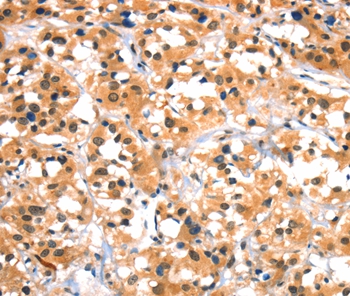

Immunohistochemical analysis of paraffin-embedded Human gastric cancer tissue using #37405 at dilution 1/30.

,

Immunohistochemical analysis of paraffin-embedded Human thyroid cancer tissue using #37405 at dilution 1/30.